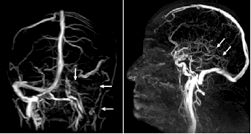

图2.左图示左静脉窦及颈静脉均无血流;

右图示深部静脉系统无血流(→)。